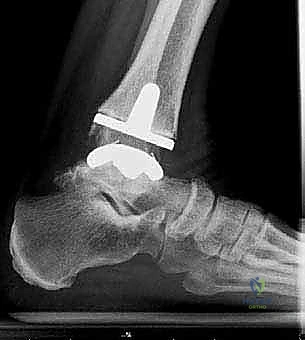

4. تركيب المفصل الصناعي (Implantation)

يتكون مفصل الكاحل الصناعي الحديث عادة من ثلاثة أجزاء:

* قطعة معدنية علوية: تُثبت في عظمة الظنبوب (الساق).

* قطعة معدنية سفلية: تُثبت في عظمة الكاحل.

* قطعة بلاستيكية (بولي إيثيلين عالي الكثافة): توضع بين القطعتين المعدنيتين لتنزلق بسلاسة وتمتص الصدمات، محاكيةً وظيفة الغضروف الطبيعي.

يتم تثبيت هذه الأجزاء بإحكام (إما عن طريق الضغط المباشر لتشجيع نمو العظم حولها، أو باستخدام أسمنت طبي خاص).